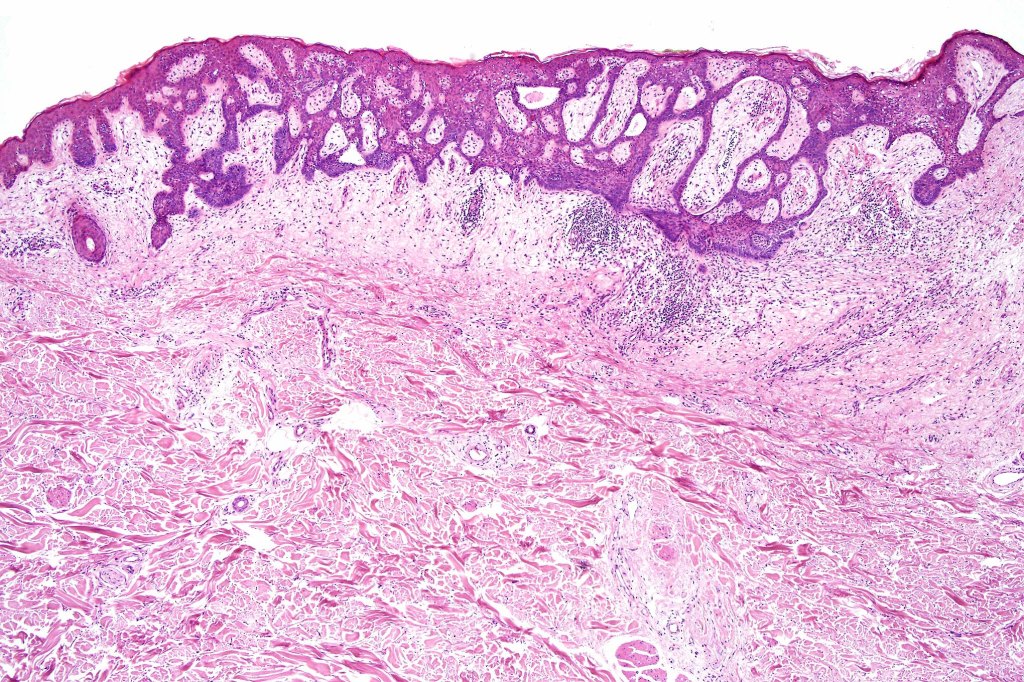

Histological features

•Characteristic fenestrated epithelial plate-like silhouette suspended below the epidermis

•Pale-staining epithelial cells with peripheral palisading

•Eosinophilic basement membrane

•No pleomorphism or mitotic activity